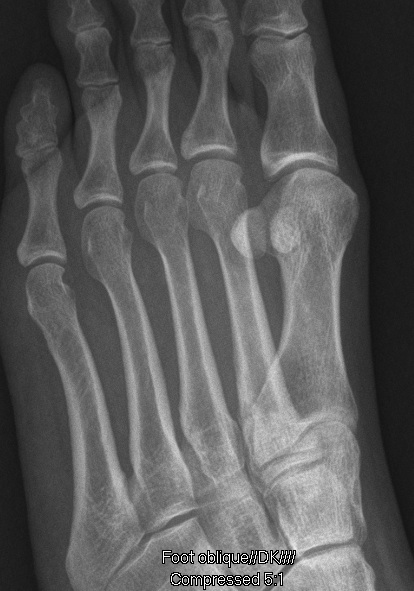

Met Fracture #1 Blog

Oblique X-Ray view